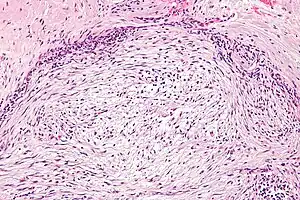

The microscopic histopathology of hematoxylin and eosin stained nodular fasciitis tumors (see above and three below figures) consists of spindle-shaped myofibroblastic cells (i.e. cells with features of smooth muscle cells and fibroblasts.).[9] These cells are in a myxoid (i.e. more blue or purple compared to normal connective tissue because of excessive uptake of the hematoxylin stain) or a collagenous (high content of collagen fibers) tissue background. The neoplastic myofibroblasts are arranged in whorls and/or short bundles. These cells may show high rates of replicating as judged by their mitotic index but these mitoses are normal in appearance. The tumor tissues often contain red blood cells, lymphocytes and giant osteoclast-like giant cells and may contain sites of bone-like tissue.[11] NF is sometimes classified into three subtypes based on its predominant histopathological pattern: myxoid or reactive (type I), cellular (type II), and fibrous (type III).[5] These patterns appear related to the duration of the lesion with the myxoid variant tending to have the shortest duration and the cellular and fibrous variants tending to have progressively longer durations.[15]Immunohistochemical analyses indicate that the cells in NF usually express smooth muscle actin, muscle specific actin, and vimentin proteins but generally do not express CD34, S-100 protein, desmin, trypsin, factor VIII, F4/80 (also termed macrophage-specific antigen), or HLA-DR1 proteins.[11] Uncommonly, the cells in NF tumors also express the CD68 (a histiocyte-specific marker) protein.[5]

Goldner, 400x